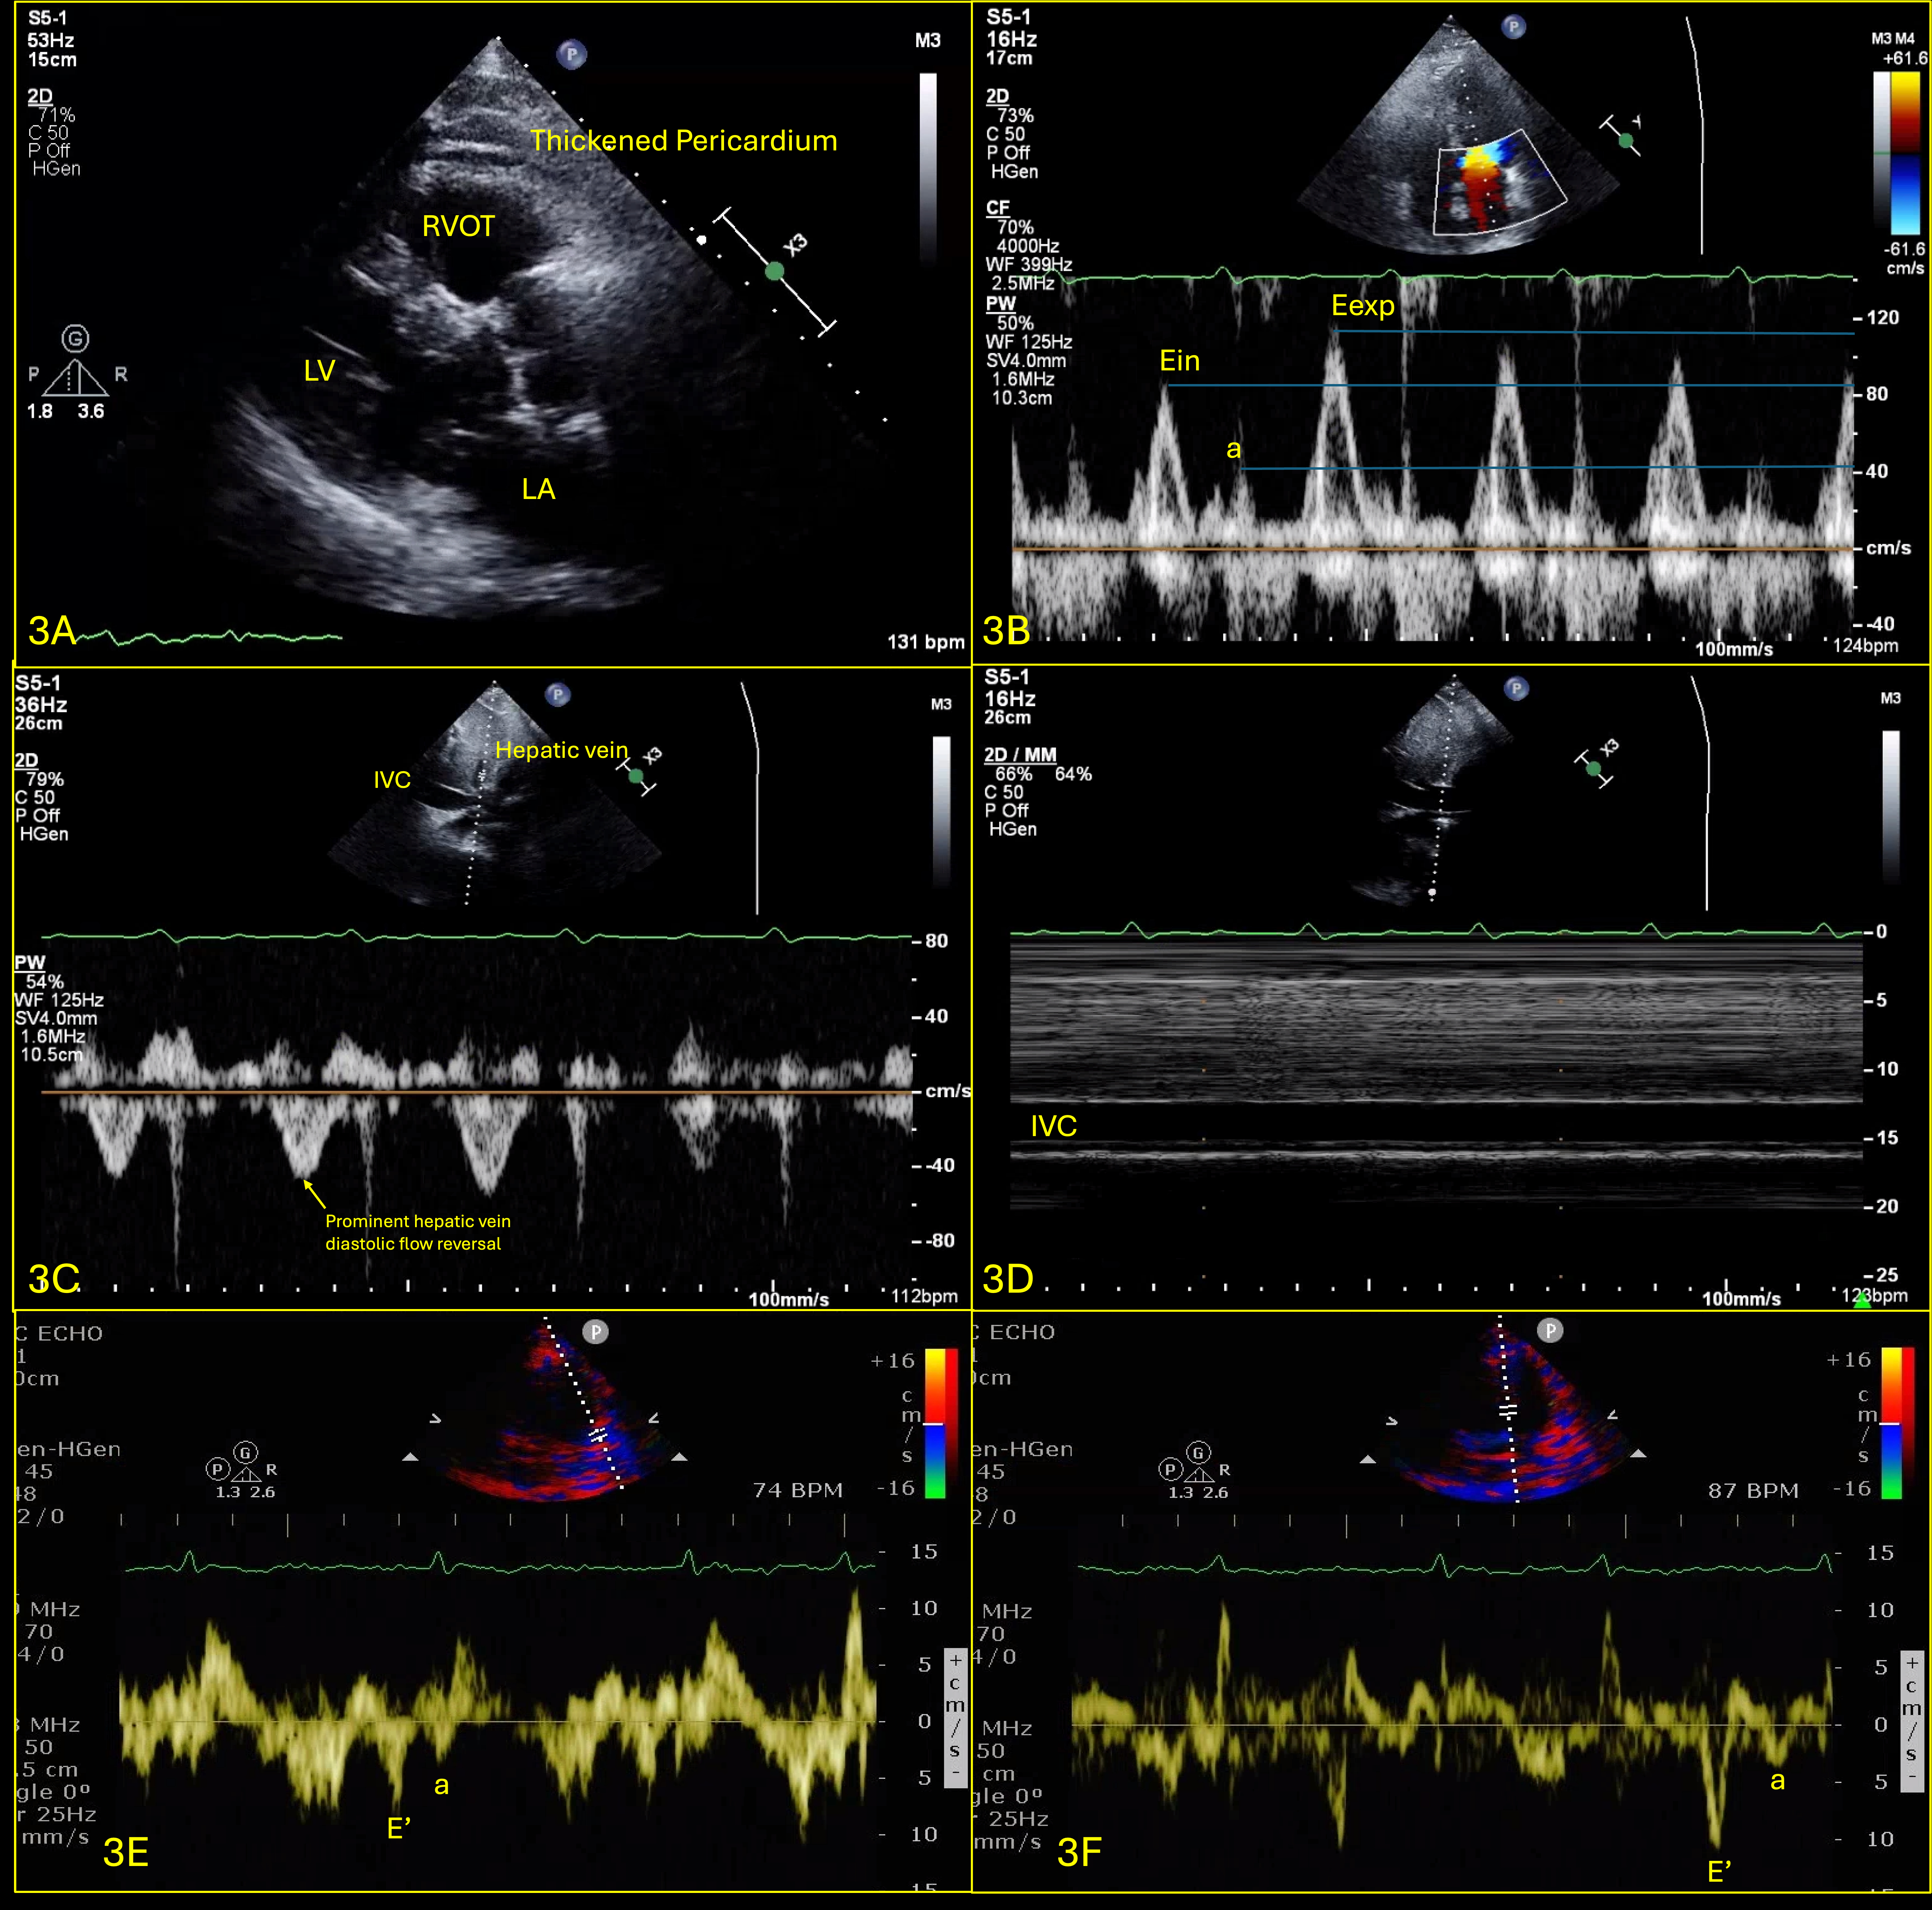

Abstract Body (Do not enter title and authors here): Case Presentation: A 76-year-old male, non-smoker, with history of HLD and NIDDM, presented with several weeks of dyspnea and cough, unresponsive to outpatient treatments. He was normotensive and found to have new onset atrial fibrillation at a rate of 110bpm and pulsus paradoxus with a difference of 15mmHg. CT chest showed a 2.2cm thyroid nodule along with a pericardial effusion (PE), confirmed to be tamponade on TTE (Fig.1). A TTE showed resolution of tamponade after the pericardial window (Fig.2). Pericardial fluid cytology was positive for malignant cells. Patient was discharged, had an outpatient PET CT which showed uptake in the thyroid, pericardial region & right supraclavicular lymph node (LN). The patient developed symptoms of heart failure, prompting his 2nd visit to the hospital after 3 weeks. A repeat TTE showed a small PE with effusive-constrictive physiology (Fig.3). He was started on high dose steroids and diuresed as tolerated, but his symptoms did not improve. He underwent thyroid nodule and right supraclavicular LN biopsy, which revealed high grade follicular thyroid carcinoma (FTC). His course was complicated by multiorgan failure, prompting transfer to another facility for pericardiectomy; during which he was found to have extensive tumor infiltration into the myocardium; he then went into shock and passed away shortly after.

Discussion: Effusive-constrictive pericarditis (ECP) is a rare clinical condition characterized by PE with constrictive physiology1. Hancock defined ECP as a pathophysiological form of cardiac compression due to a constricted visceral pericardium and PE, with the hallmark sign of persistently elevated right atrial pressure despite removal of pericardial fluid2. ECP can rarely be caused by malignancies, attributing 5% of cases2. FTC is a well-differentiated thyroid malignancy that typically metastasizes to distant sites such as the lungs and bones, but pericardial involvement is extremely rare. To date, there has been one reported case of PE caused by FTC, but the PE did not reaccumulate, possibly due to early recognition and radiation therapy3. To our best knowledge, this case report represents the first documented case of ECP caused by FTC. Our case demonstrates the complexity of diagnosing/managing it, which underscores the need for a multidisciplinary approach and comprehensive diagnostic evaluation in patients with PE, especially when associated with malignancies that rarely metastasize to the pericardium.